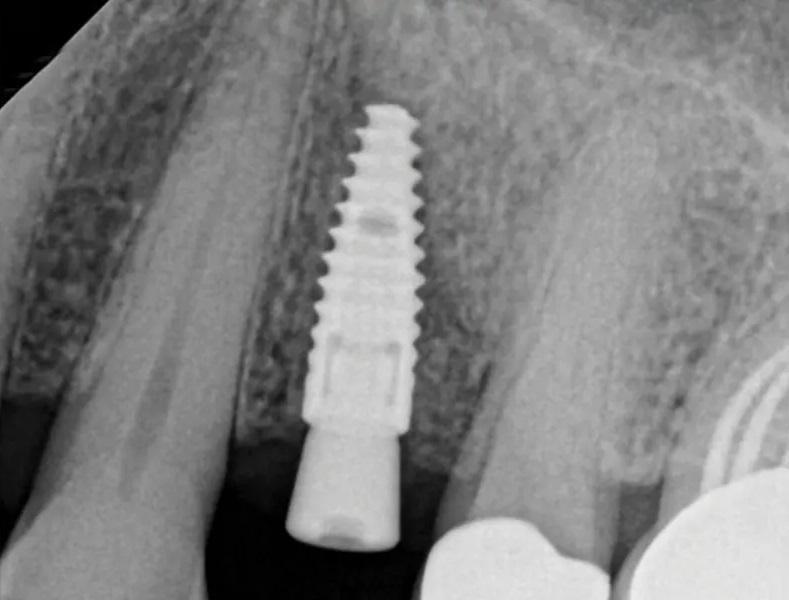

На контрольном осмотре через 16 месяцев клиническая оценка выявила сохраненный объем гребня и стабильную кератинизированную мягкую ткань (Фото 22 и Фото 23). Рентгенологический анализ подтвердил стабильный уровень кости вокруг имплантата № 2.4 и положительные рентгенологические изменения, свидетельствующие о регенерации тканей на медиальной поверхности зуба № 2.5, включая восстановление периодонтальной связки (Фото 24).

Фото 24. На контрольном осмотре через 16 месяцев: ПА рентгеновский снимок показывает стабильный уровень краевой кости, патологии не выявлено.